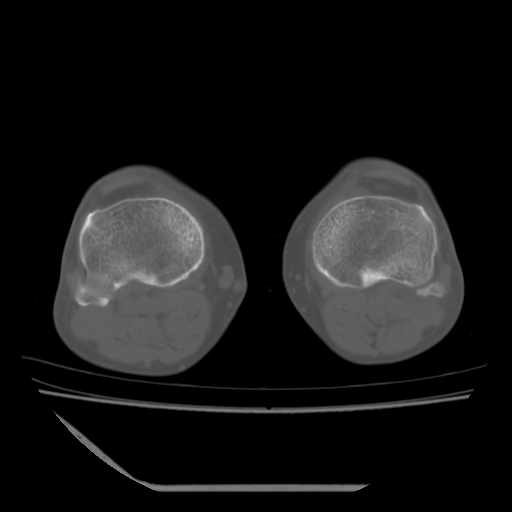

标题: CT13225:老年男性,左膝关节疼痛数月;请各位老师讨论。 [打印本页]

标题: CT13225:老年男性,左膝关节疼痛数月;请各位老师讨论。

骨质增生,骨性关节面硬化,关节积液,考虑退行性骨关节病

关节腔内少量积液,关节面退变。

双膝退变

骨质增生,骨性关节面硬化,关节间隙失常,关节积液,考虑退行性骨关节病.

这是由于两侧的肌肉不对称所致,加上扫描的平面也有些差异。请看示意图:

这个病例诊断:退行性骨关节炎